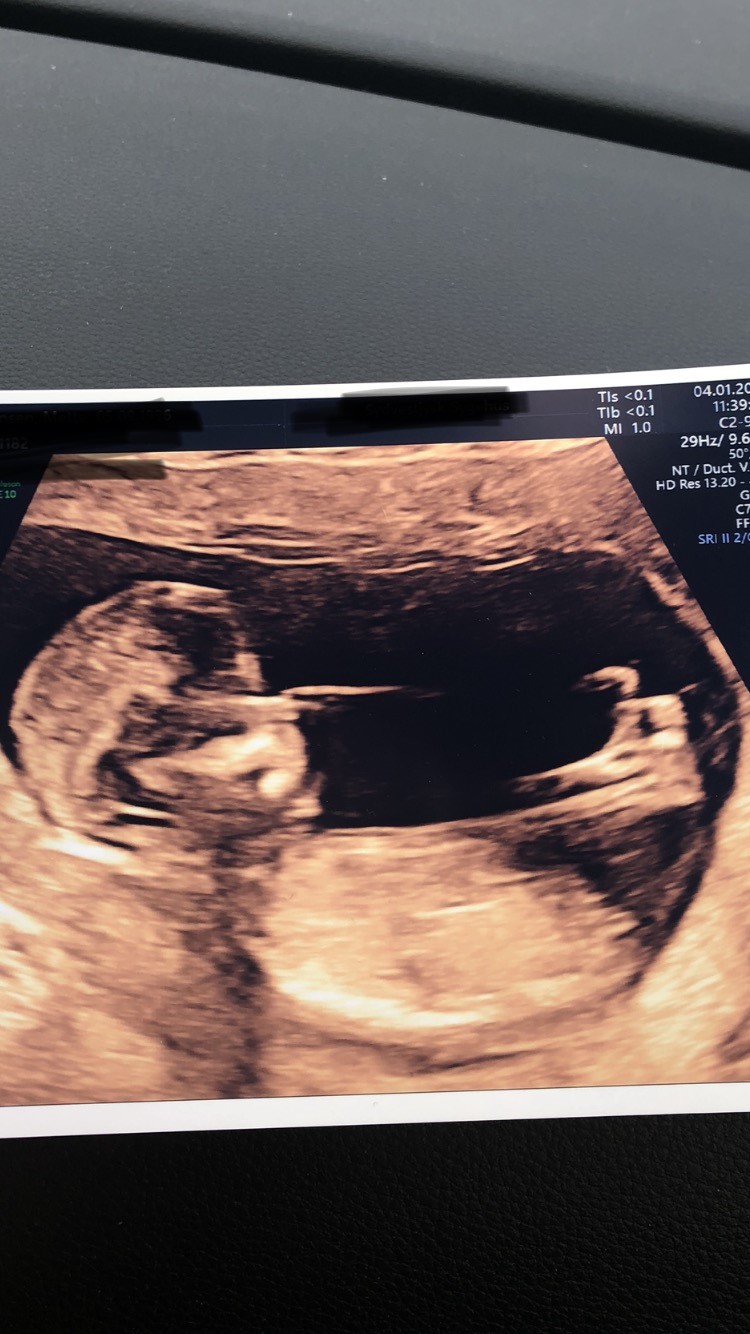

Jeg har fået lavet nakkefoldsscanning i 12+6. Jeg skal til kønsscanning i næste uge, men jeg er så nysgerrig! Er det nubben der kan ses på billedet? I såfald hvad køn ligner det så? ��

Vedhæftede fotos (klik for at se i fuld størrelse)